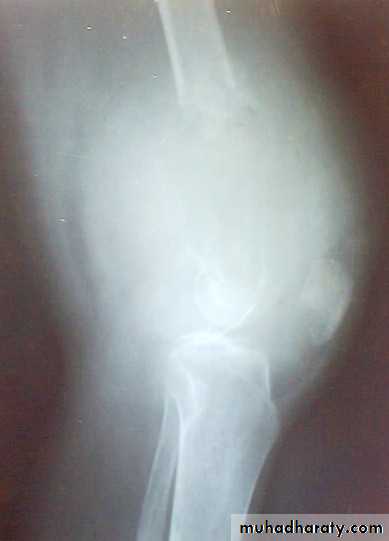

Giant cell tumor

Patient presented by local pain and swelling or pathological fractures. Common site is the distal femur, proximal tibia, distal radius.

X-ray show eccentric osteolytic lesion in the end of long bone ,subchondral, trabeculated (soap bubble appearance). The cortex is thin, expanded or even perforated.